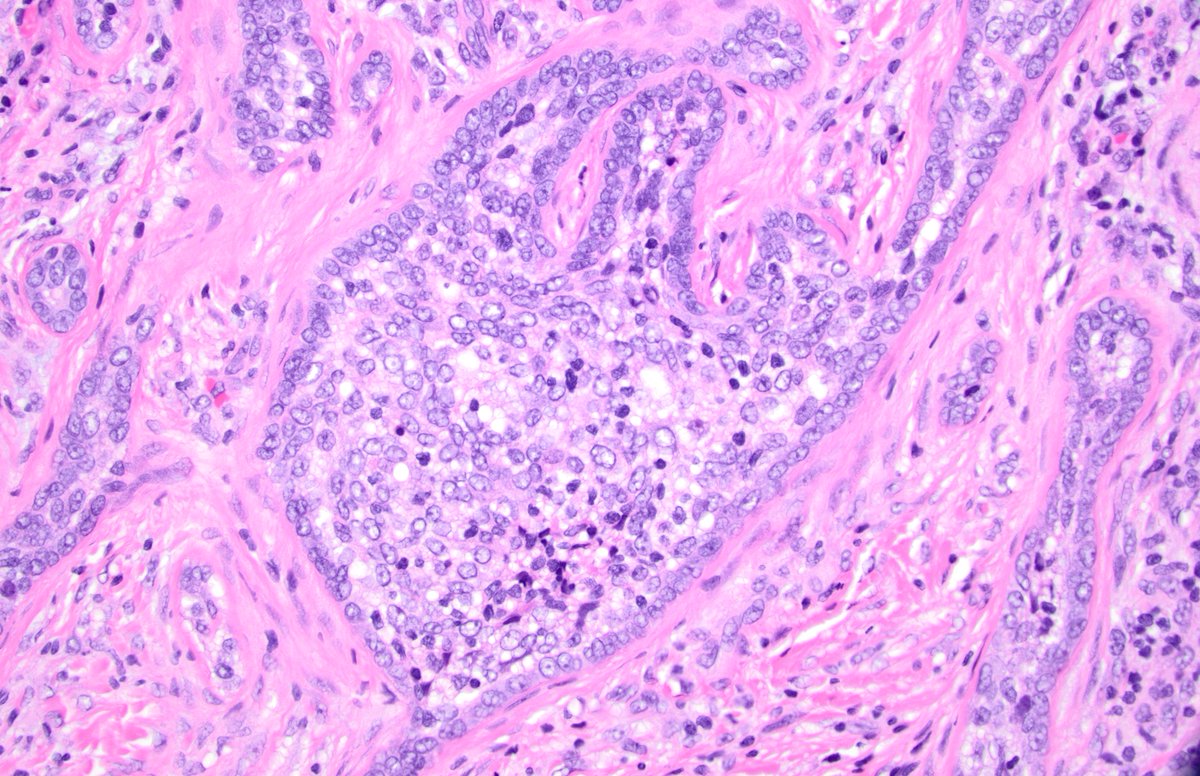

CSPEI 25-6: 63-year-old female with postmenopausal bleeding and total hysterectomy with bilateral salpingo-oophorectomy. ❓ Question: What is the origin of the tubulo-glandular abnormalities? ✍️ Author: Maryam Sharifian, MD Please follow, like, comment, & repost! 🙌

1

2

7